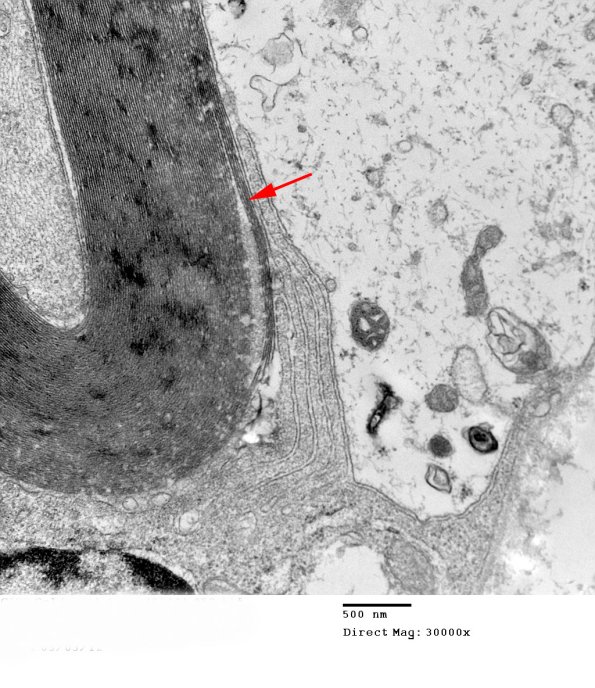

The pale Schwann cell cytoplasm may be a feature of this case. Notice the multiple macrophage processes peeling off the myelin (arrow)